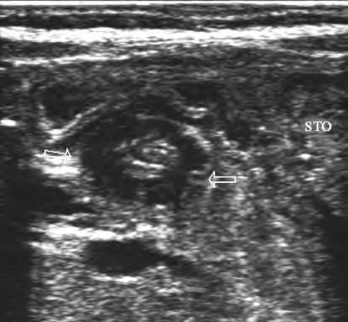

婴幼儿常见病,系幽门环形肌肥厚,造成幽门狭窄而发生的不全梗阻(图27-7)。

1.婴幼儿幽门壁呈全周性、均匀性增厚,厚度≥0.4cm,幽门管长度>1.8cm,横切面前后径>1.5cm(正常婴儿幽门壁厚0.1~0.3cm,幽门管长0.5~1.4cm,幽门前后径0.7~1.3cm)。

2.幽门管腔狭窄,液体通过受阻,胃腔内可见潴留物。

图27-7 先天性肥大性幽门狭窄声像图

患儿幽门括约肌呈环形均匀增厚,造成幽门狭窄(箭头)。STO:胃